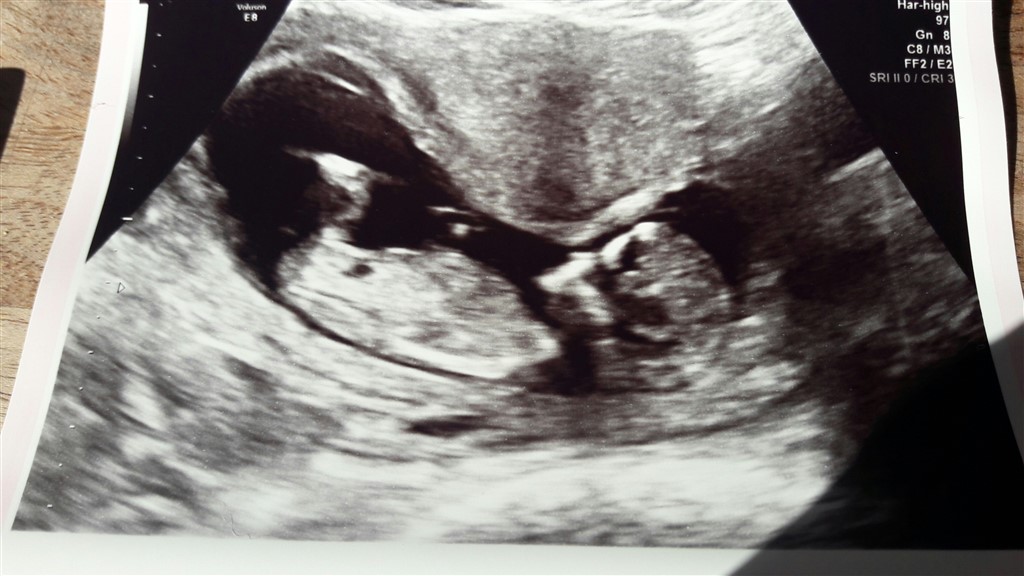

NF gennemført og alt okay. Termin 13/10

Vedhæftede fotos (klik for at se i fuld størrelse)